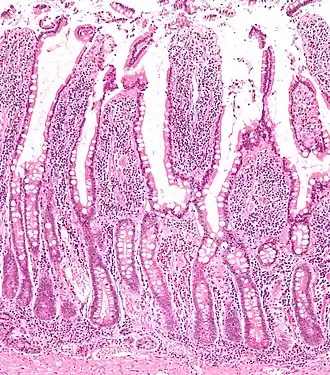

![]() Section of duodenum of a cat. X 60. | |

Intestinal villi (sg.: villus) are small, finger-like projections that extend into the lumen of the small intestine. Each villus is approximately 0.5–1.6 mm in length (in humans), and has many microvilli projecting from the enterocytes of its epithelium which collectively form the striated or brush border. Each of these microvilli are about 1 μm in length, around 1000 times shorter than a single villus. The intestinal villi are much smaller than any of the circular folds in the intestine.